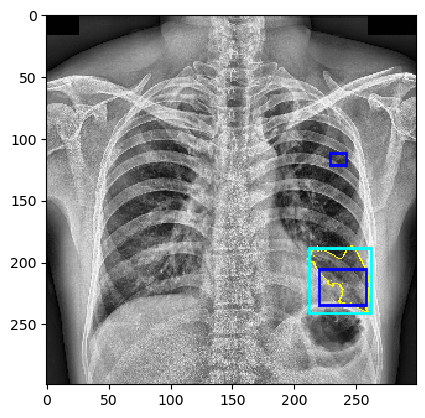

The behavior of MindfulLIME compared to LIME is demonstrated in Figures 4 and 5. Figure 4 showcases random sample 1 with a detected Pleural Effusion condition (annotations highlighted in green), while Figure 5 features random sample 2 with a detected Lung Opacity condition (annotations highlighted in blue). Each figure illustrates the disparities between the ground-truth annotations (darker-colored rectangles) and the generated explanations (lighter-colored rectangles surrounding the yellow border of the selected superpixels). We would like to emphasize that our trained classifier model generalizes well and is not simply memorizing the training data, as evidenced by its performance on a separate evaluation dataset.

The left columns depict the results for the top 1 feature, while the right columns display the results for the top 4 features. The first row presents the output of MindfulLIME, while the second and third rows represent the results of LIME using 1000 and 4000 samples, respectively. When comparing the results of LIME and MindfulLIME for two visual random samples, it becomes evident that MindfulLIME excels in multiple aspects. Firstly, MindfulLIME consistently identifies the top 1 feature with the highest similarity with the actual bounding box. Additionally, as the number of top features increases, MindfulLIME effectively prioritizes and presents more relevant features at the forefront. These findings highlight the enhanced performance and prioritization capabilities of MindfulLIME compared to LIME.